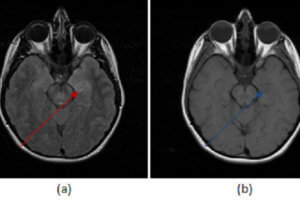

Brain Abscess

Abscess is in the differential for a rim enhancing mass, an important one in neuroradiology and often remembered by the mnemonic MAGIC DR – metastasis, abscess, glioma, infarct, contusion, demyelination and radiation... Read more »